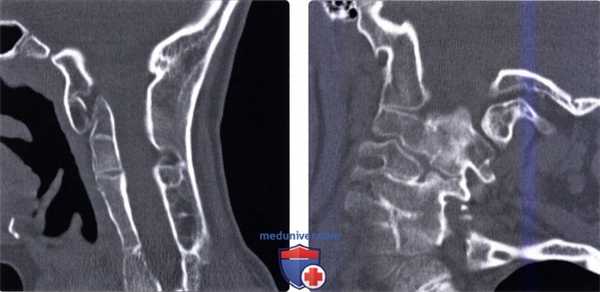

(Слева) На сагиттальной КТ (СКФ) определяется легкое нарушение сегментации на одном уровне (С4-С5). Узкая «талия» рудиментарного диска и слияние остистых отростков типичны для этой патологии.

(Справа) На корональной КТ в костном окне определяется вариант нарушения сегментации в виде крупной, хорошо отграниченной коаной «перемычки с кортикальной пластинкой (околомыщелковый отросток), соединяющей сосцевидный отроаок с поперечным отростком С1.